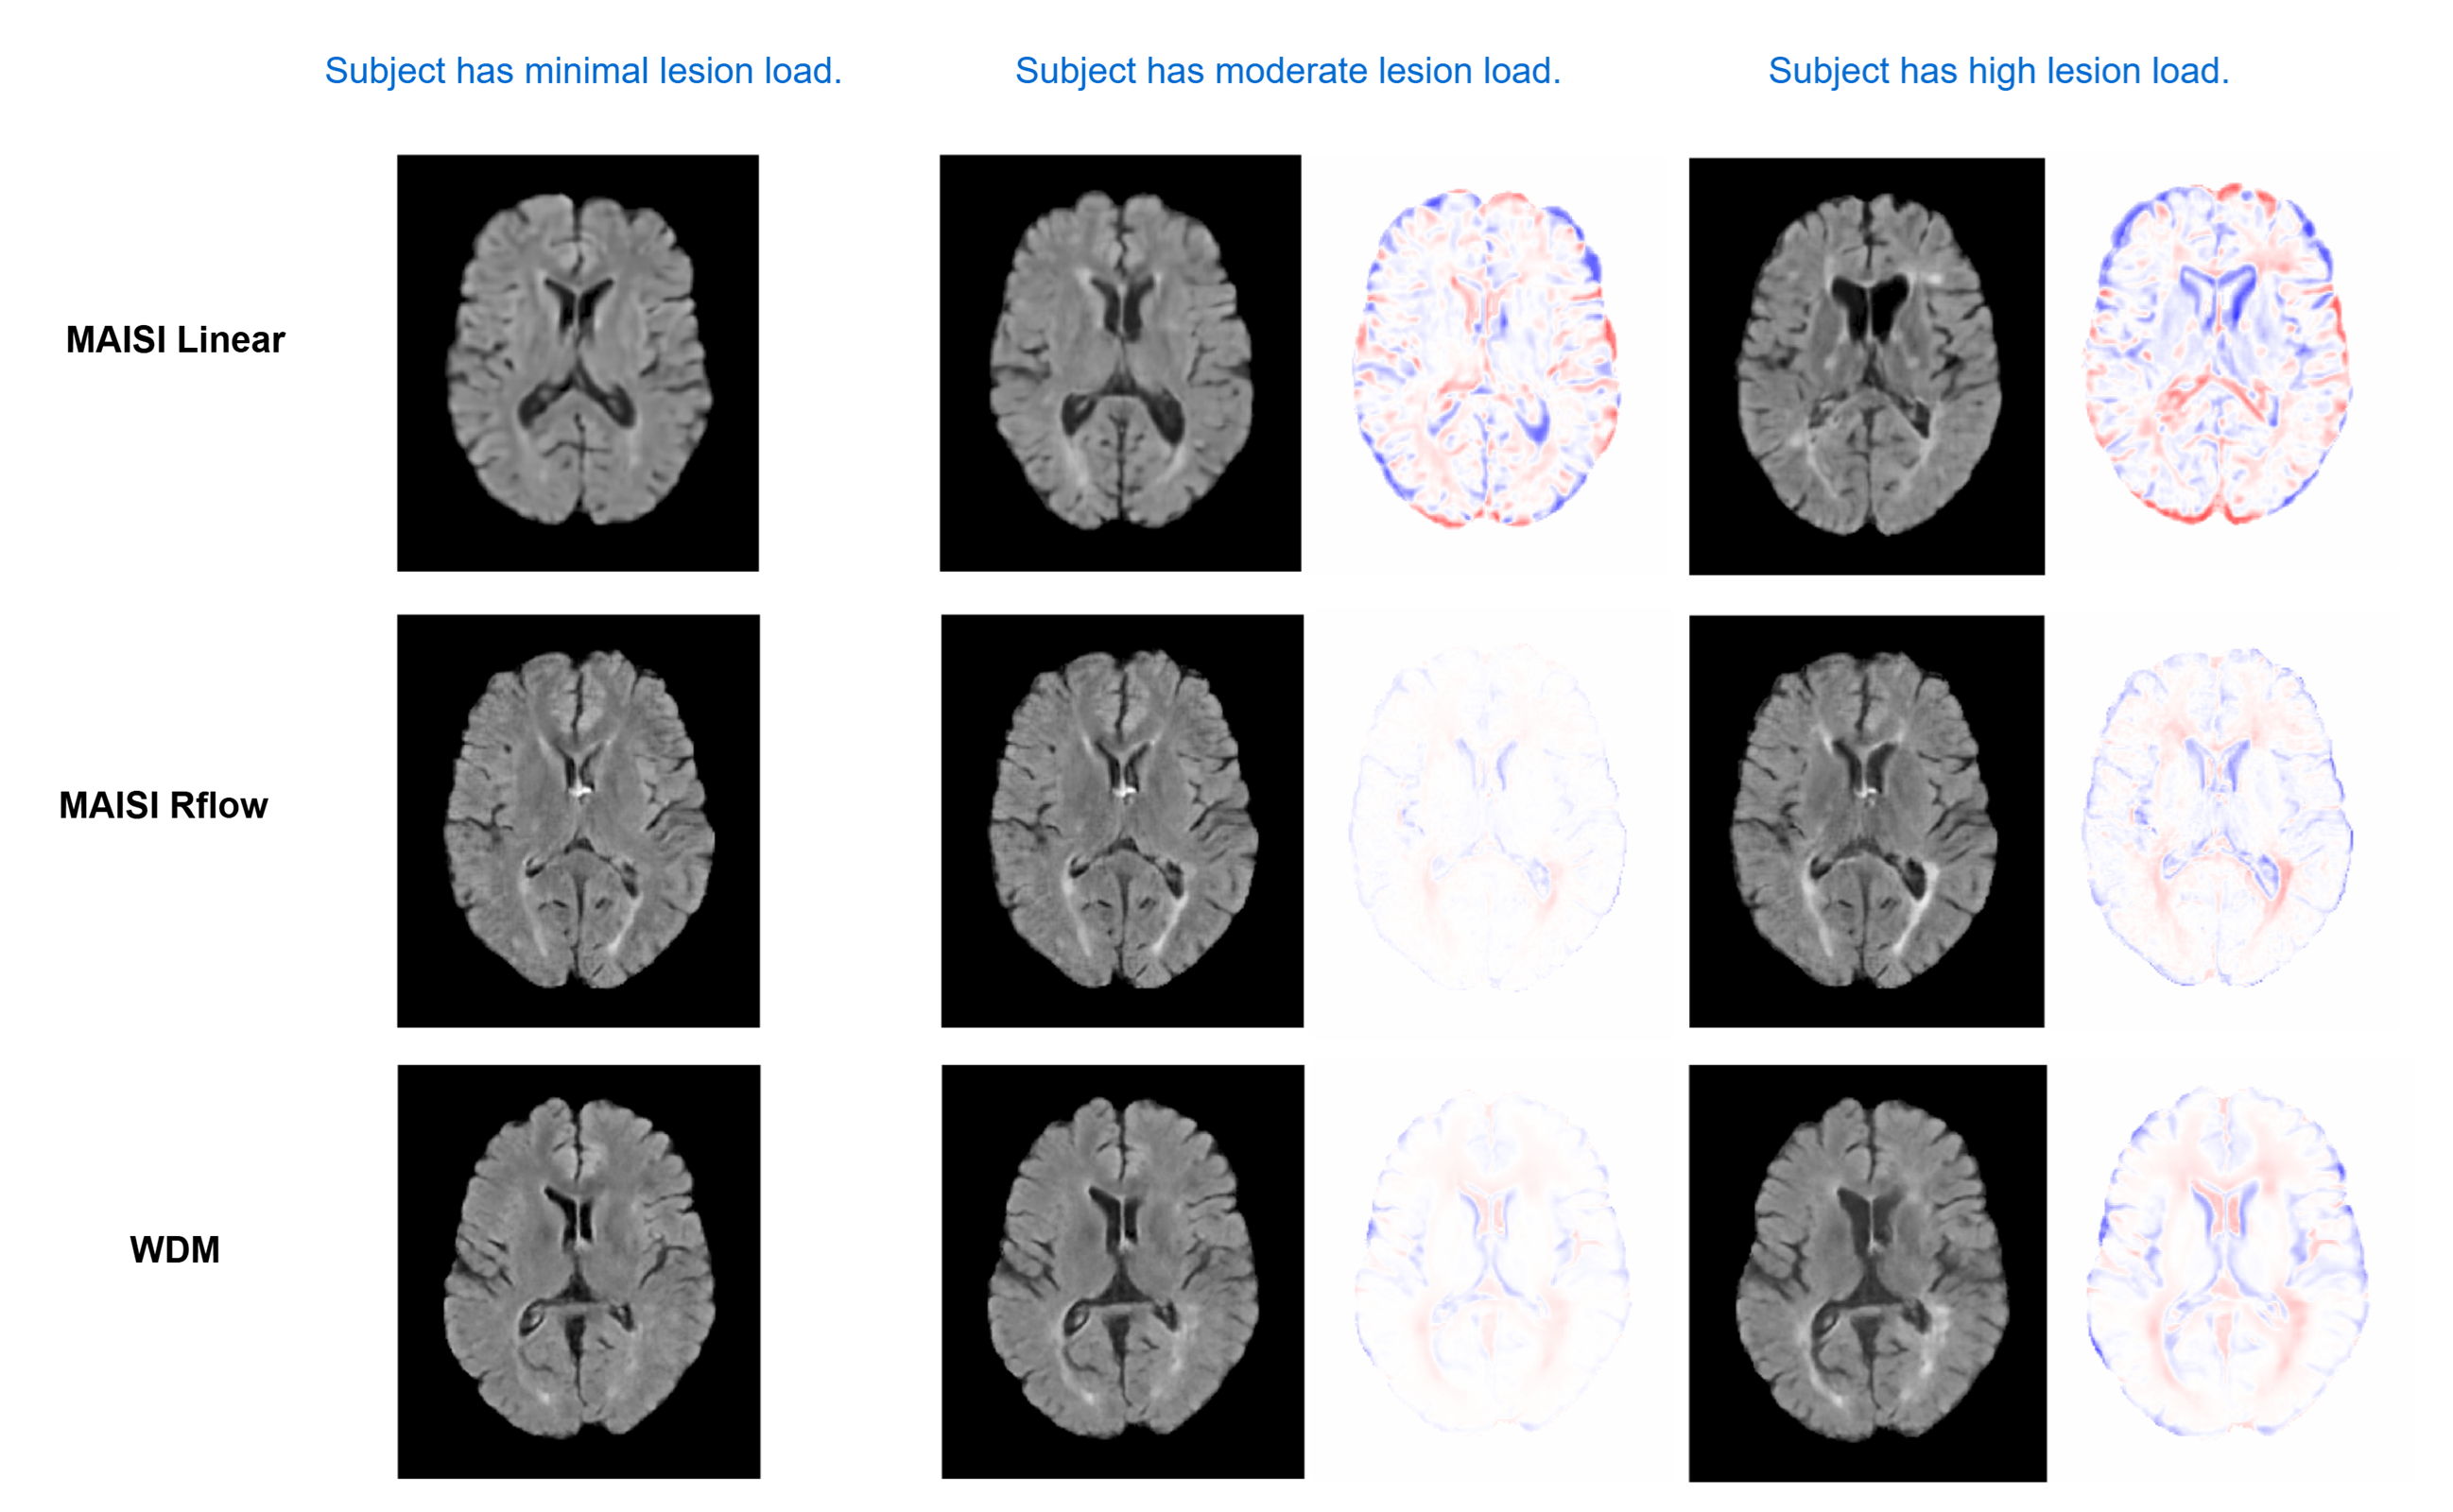

In this work, we introduced a novel vision-language framework designed specifically for generating high-resolution, text-guided 3D counterfactual medical images of synthetic neurological subjects. Our approach addresses critical limitations of existing methods by integrating advanced diffusion architectures with medically-informed semantic embeddings derived from BiomedCLIP. The results demonstrate that our language-guided wavelet-based diffusion model (WDM), operating directly in voxel space, delivers superior subject preservation, image quality, and text alignment compared to conventional latent diffusion approaches. Additionally, the MAISI RFlow model, which incorporates a Rectified Flow noise schedule, significantly improves anatomical consistency and image fidelity while achieving computational efficiency. Qualitative and quantitative analyses clearly indicate the effectiveness of these models in simulating nuanced disease-progression scenarios in synthetic patients, and our ablation studies on classifier-free guidance underscore the explicit trade-offs between prompt fidelity and anatomical accuracy.

Vision-language models have shown strong performance in 2D image generation due to extensive pretrained foundation models, but comparable models for 3D are lacking, limiting progress in medical imaging. This absence restricts applications such as counterfactual explanations, disease progression simulations, and medical training. We present a framework that generates high-resolution 3D counterfactual medical images from free-form language prompts by adapting state-of-the-art 3D diffusion models with enhanced text conditioning. To our knowledge, this is the first language-guided native-3D diffusion model applied to neurological imaging, enabling faithful representation of brain structures. Experiments on MRI datasets demonstrate the ability to simulate lesion loads in Multiple Sclerosis and cognitive states in Alzheimer’s disease, producing realistic images while preserving synthesized subject fidelity. Our work establishes a foundation for prompt-driven disease progression analysis in 3D medical imaging.